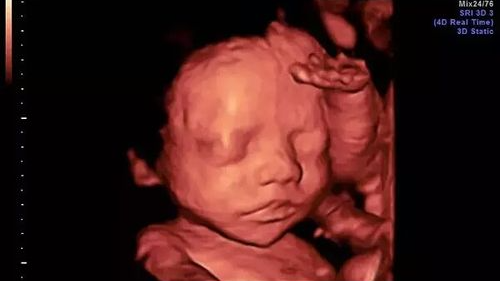

四维彩超可以直观、立体显示人体器官的三维结构及动态,实时地观察立体结构,所以准妈妈们还可以看到胎儿在母体内微笑、咬手、踢腿、伸懒腰、打哈欠的调皮可爱模样。